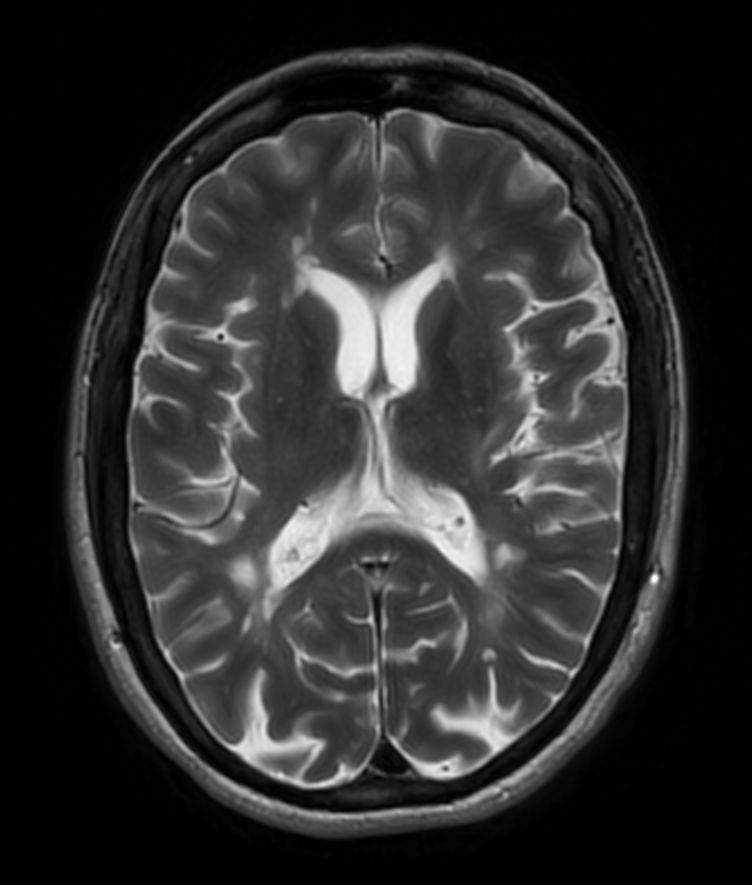

T2w TSE MultiVane XD